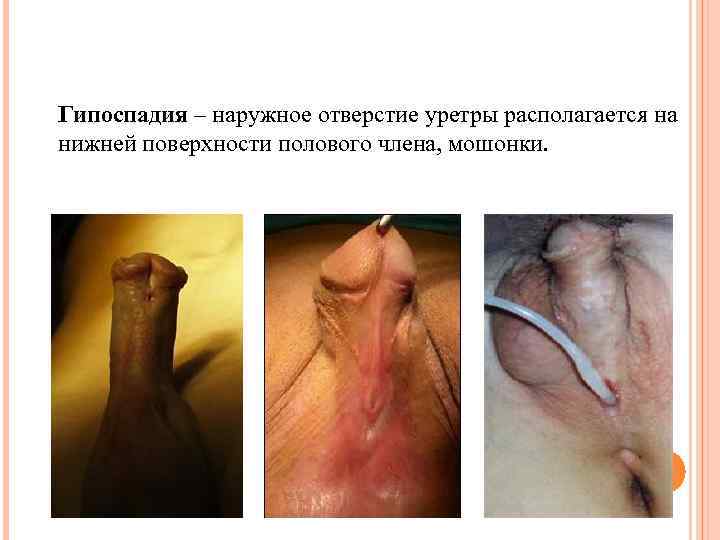

Гипоспадия – наружное отверстие уретры располагается на нижней поверхности полового члена, мошонки.

Гипоспадия – наружное отверстие уретры располагается на нижней поверхности полового члена, мошонки.